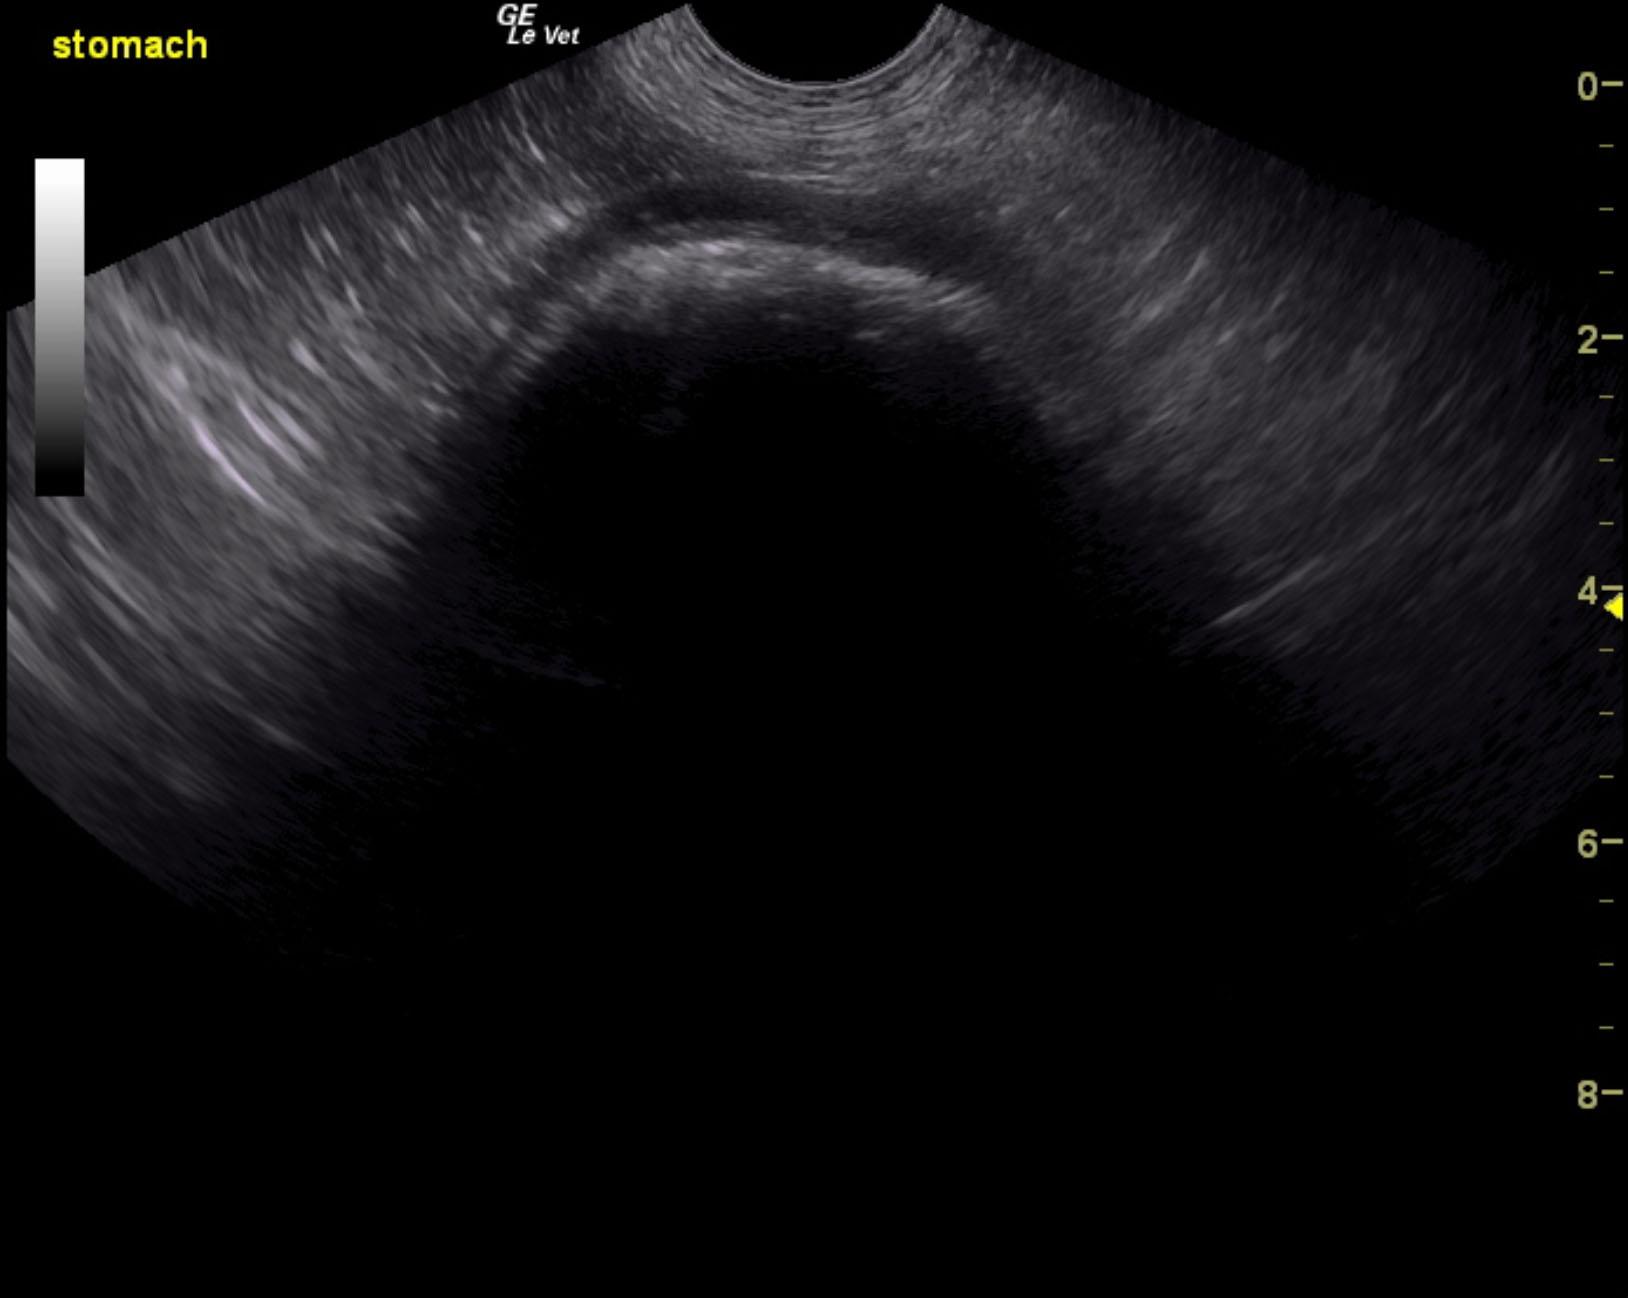

The patient is a canine Rottweiler, NM, 10 years, 105.8 lbs. who was presented for weight loss, occasional v/d, history of eating rugs/carpets and dog beds on multiple occasions, however this is a new behavior change. No vomiting currently. Urine specific gravity 1.025, pH 6.5.